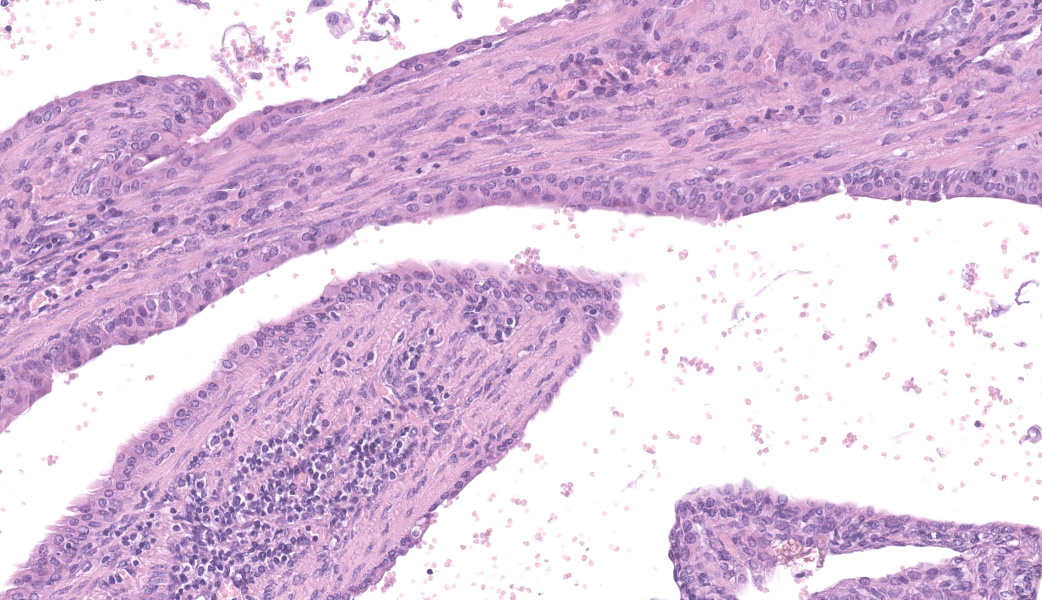

Left kidney: The left kidney is composed of multiple, largely dilated cavities that divide the kidney into numerous islands of parenchyma. These cavities are lined by 2–4 layers of cuboidal to highly columnar, eosinophilic epithelial cells with no mitotic activity (collecting ducts). Few sloughed epithelial cells and erythrocytes are present in the lumen of these ducts. The parenchyma contains islands of immature glomeruli with peripheral nuclei, poorly developed capillaries, and thickened Bowman’s capsule (vimentin positive). Primitive tubules are lined by large basophilic cuboidal epithelial cells with minimal or absent lumina. Other areas within the parenchyma consist of mature tubules and glomeruli with some tubules showing mild dilation and intraluminal protein casts. Collecting duct-like structures are multifocally surrounded by loosely arranged mesenchymal tissue (primitive mesenchyme). The interstitium is multifocally expanded by fibrous connective tissue and some areas are infiltrated by low to intermediate numbers of lymphocytes, plasma cells, macrophages, and occasional neutrophils. Some arteries are very prominent (large) with thickened media, and they appear tortuous. A medium sized artery is surrounded and infiltrated by inflammatory cells predominantely macrophages, neutrophils and occasionally multinucleated giant cells within adventitia, media and intima (transmural). Diffuse proliferation of fibroblasts and deposition of fibrin within the vessel wall is observed. Occasionally, the tunica intima is disrupted. Endothelial cell proliferation is evident with clustering of endothelial cells attempting to recanalize the affected lumina.

The large number of fetal glomeruli, presence of few primitive tubules, and occasional primitive mesenchyme, especially in a 5-week old mouse, certainly suggest a degree of renal dysplasia. Mouse kidneys should be completely developed within 4 days of birth (no later than 7 days).1,5 However, there was debate amongst conference attendees on whether this was a primary renal dysplasia or a secondary delay in maturation due to atrophy caused by congenital hydronephrosis/hydroureter. The fetal glomeruli were strikingly obvious in this case and are characterized by a reduction in the number of capillaries, the presence of podocyte nuclei that palisade around the periphery of a small glomerular tuft, decreased tuft segmentation, and a thick Bowman’s capsule. Immature glomeruli are, in a not-so-convoluted kidney, usually best seen in the subcapsular cortex.1,5 Glomeruli aside, however, while there were rare definitively primitive tubules, most participants thought that many of the tubules were atrophied in response to the severe hydronephrosis rather than truly dysplastic. This was further complicated by the complete lack of medullary distal convoluted tubules. Additionally, there were occasional glomeruli that were mature and the majority of the scant interstitium was relatively developed. As such, many conference participants preferred the term “asynchronous maturation” to describe the spectrum of development seen within the kidney.

The flocculent, cystic spaces made definitive interpretation of this case challenging. The lining of the cystic spaces resembled either persistent metanephric ducts (ducts in the outer medulla lined by pseudostratified, ciliated, columnar epithelium), transitional urothelium, and/or serosa. Metanephric ducts in the medulla potentially represented persistent, incompletely differentiated ureteric bud branches that did not differentiate into normal collecting tubes as they are supposed to, further suggesting a congenital etiology in this condition.5,10 The presence of serosa-lined spaces implies that some cysts had collapsed in on themselves during processing. Everyone unanimously agreed, however, that this was not polycystic kidney disease.

Differentiating between cystic renal dysplasia and polycystic kidney disease can be challenging, but there are some key differences to be aware of. Cystic renal dysplasia (CRD) is the most common pediatric renal disease in humans (and is also more common in most animals). It typically has larger cysts that are variably sized and lined by flat-cuboidal epithelium. CRD usually results from urinary tract obstruction and is often unilateral. It occurs sporadically and does not have a defined inheritance pattern like PKD. The characteristic findings for renal dysplasia will be present (fetal glomeruli, primitive tubules, primitive loose mesenchyme, +/- cartilaginous metaplasia, +/- mesenchymal collarettes), and there may or may not be vascular changes.4,10